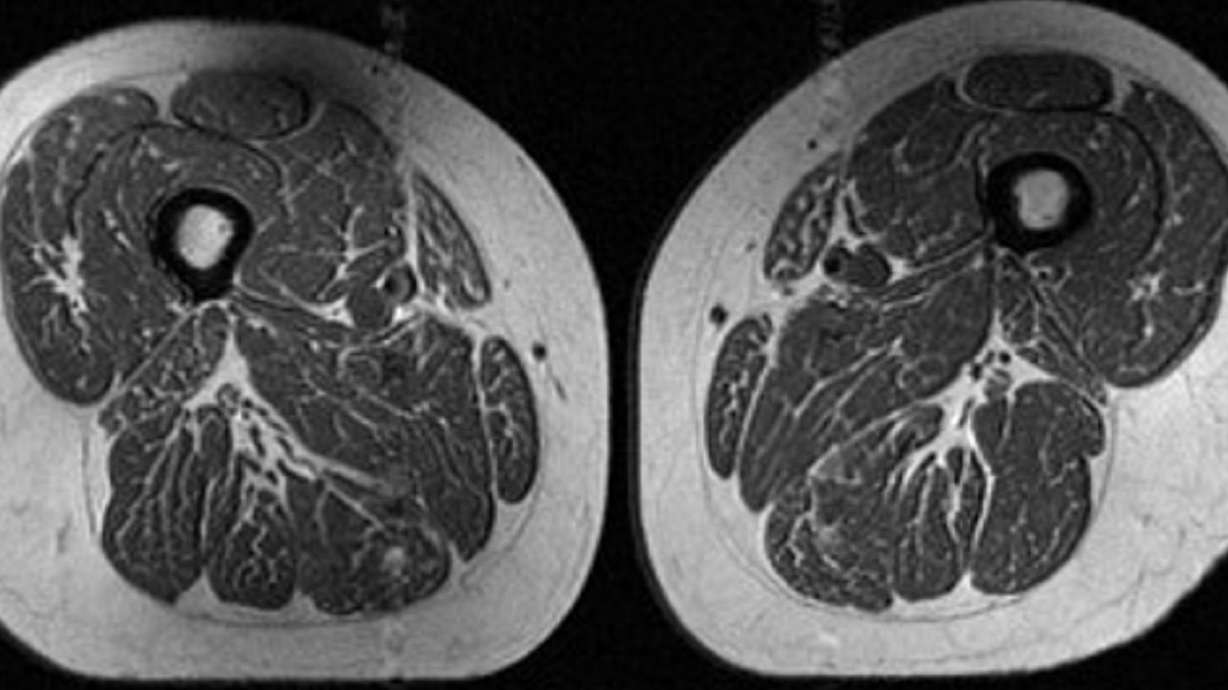

NEW YORK CITY — The image looks like a slice of highly marbled flesh, reminiscent of a high-end steak with abundant fine-grained streaks of fat. But that's not dinner. It's an MRI scan of the thigh of a 62-year-old woman who obtained 87% of her annual calories from ultraprocessed food.

A 61-year-old woman in the study also had fat marbling in her thigh muscles, but it was not as intense. About 29% of her annual diet consisted of ultraprocessed foods.

The 61-year-old woman with a diet consisting of 29.5% ultraprocessed food had a slightly higher BMI of 32.6 and a much lower activity score than the woman with a BMI of 31.8 whose diet was 87.1% ultraprocessed. Yet the woman with the higher ultraprocessed score still had dramatically more fat marbling in her thighs.